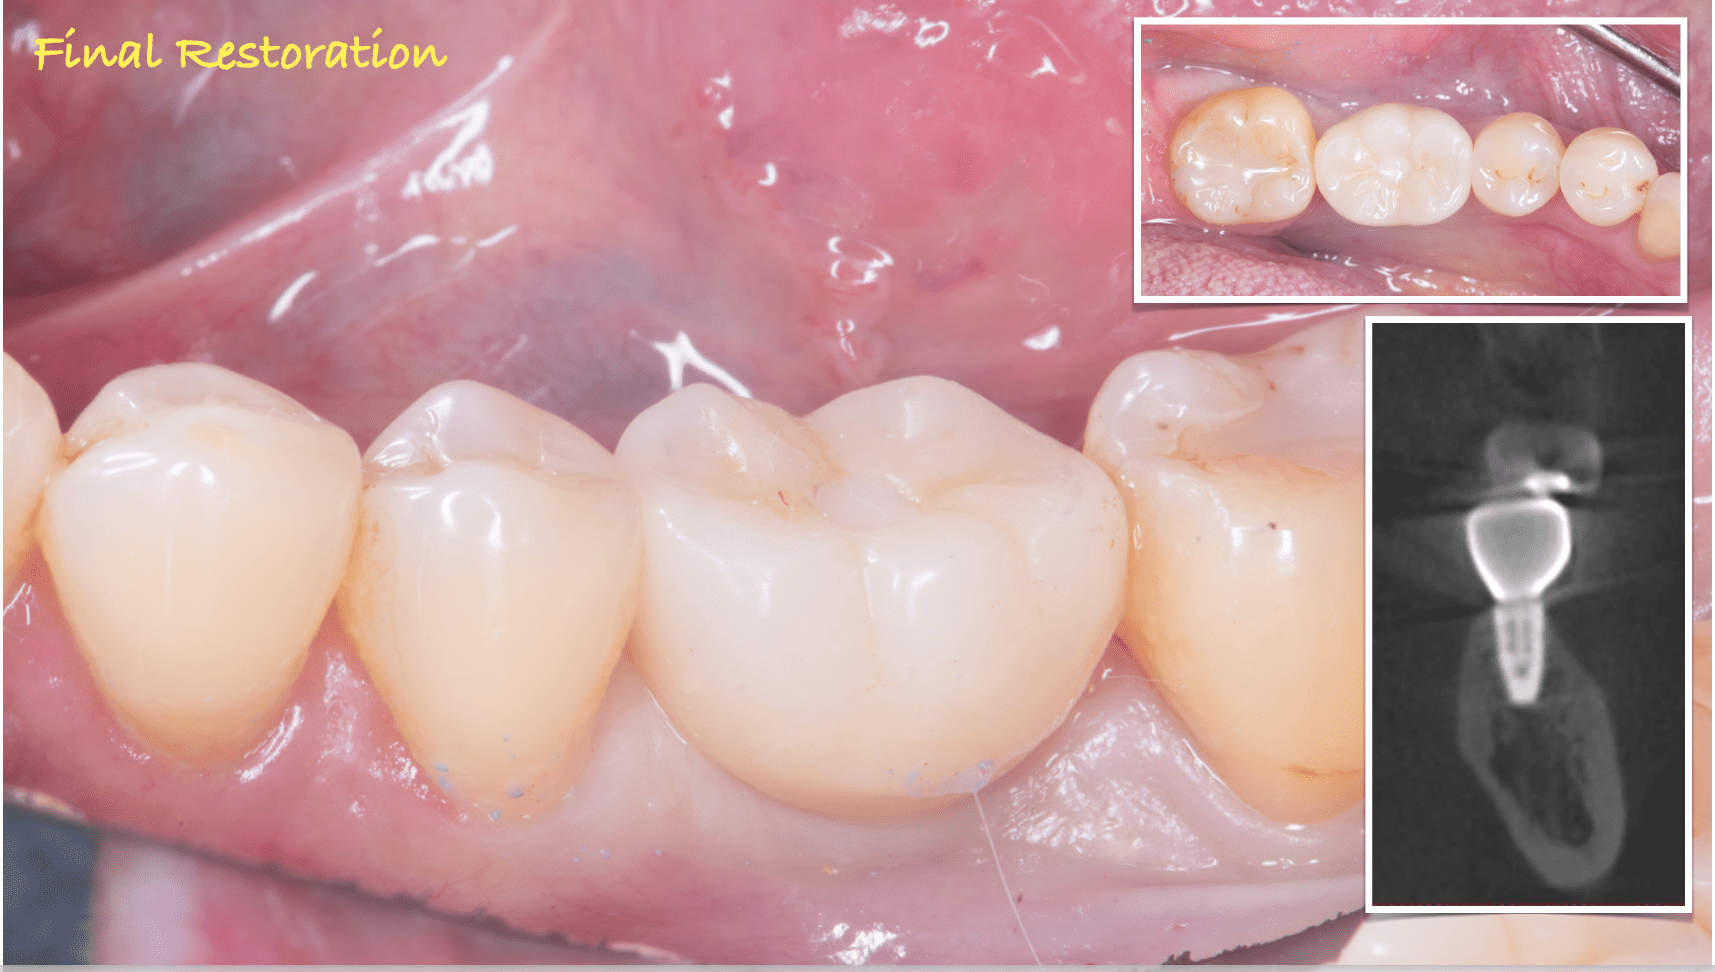

治療を終えて

最終補綴

下顎:フルジルコニアスクリューリテイン

治療のリスクと副作用

治療期間:3ヶ月

治療費:¥462,000(税込)

リスク:インプラントを正確に入れることによって、セラミックの破折を最小限に抑えることができます。